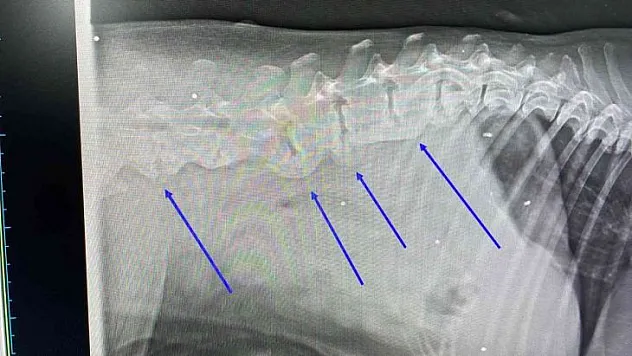

Ezilen köpeğin röntgeninden 400 saçma çıktı